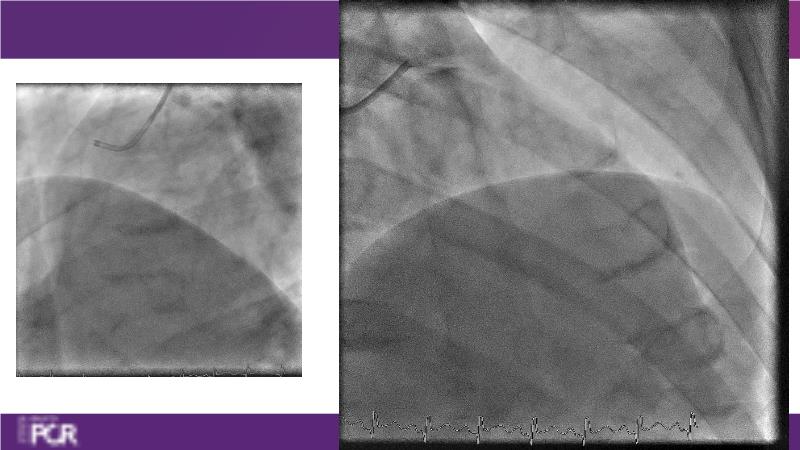

Join this session to delve into the unmet needs concerning drug-eluting stents (DES), including poor long-term clinical outcomes, with up to a 50% MACE rate at 10 years, and a non-plateauing 2-3% annual event rate. Explore how DynamX Bioadaptor technology addresses these challenges by maintaining the established flow lumen and restoring hemodynamic modulation of the artery. Discover the sustained clinical benefits demonstrated in a 2-year RCT, potentially establishing a new treatment standard for CAD patients. Gain insights into patient types benefiting most in clinical practice, such as those at higher risk of restenosis (e.g., LAD disease, long lesions, small vessels, co-morbidities), and younger patients with longer lifespans.

- To understand existing level of broad clinical experience around the world and how clinical decisions are made